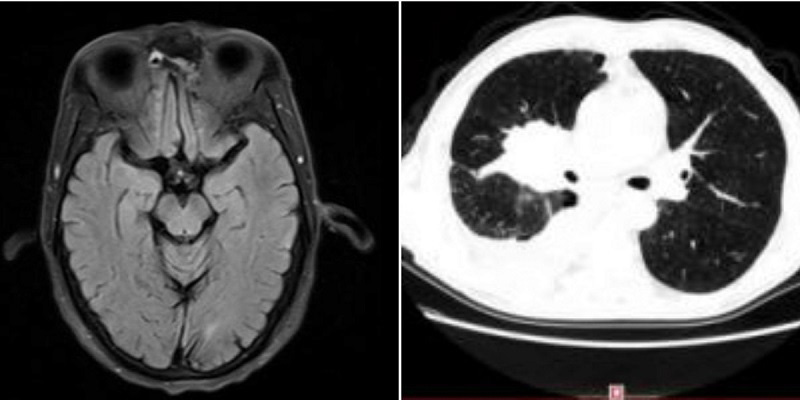

·2017年2月,李先生返回瑞康医院肿瘤科二区进行复查,复查结果提示:病灶较前缩小,脑转移瘤消失。

·2018年4月8日,李先生再返院复查,肺部肿块明显缩小。

·2020年3月26日,李先生出现头晕症,检查发现脑部出现病灶,侯主任又为李先生行脑转移瘤射波刀治疗(3f)。

·2021年3月16日,李先生返院复查,检查结果提示:右肺肿瘤明显缩小,且李先生病情稳定。建议李先生继续服用中药并可回当地医院继续贝伐维持治疗。